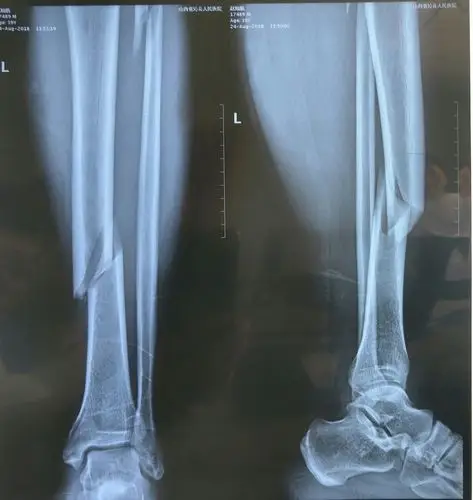

胫腓骨骨折闭合复位髓内钉固定两例